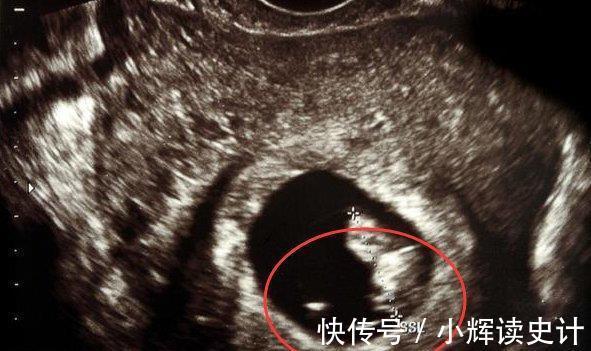

对于正常的宫内妊娠来讲,一般B超检查在

孕6-7周时,

即可见到宫内胎芽及胎心管搏动。如果超过孕七周仍没有胎芽及胎心,孕妈妈要考虑胚胎停止发育可能,应及时到医院检查胎儿的情况。

一般来说,8-10周左右去做B超就有胎心,不过过早做B超,是不容易见孕囊的影子,太小了。